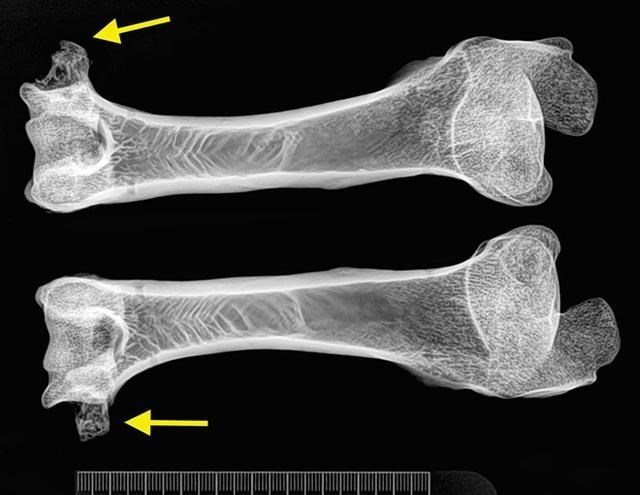

在它两岁的时候与一只威尔士山羊交配 , 先后生下了六只小羊羔 。 等到多莉5岁的时候 , 它就患上了关节炎 , 这是一种在老年绵羊中十分普遍的疾病 , 因为绵羊的寿命一般为12岁左右 , 所以老年绵羊患上关节炎的年龄一般是9~10岁 , 多莉仅在五岁就患上关节炎这是一个十分值得重视的事情 。